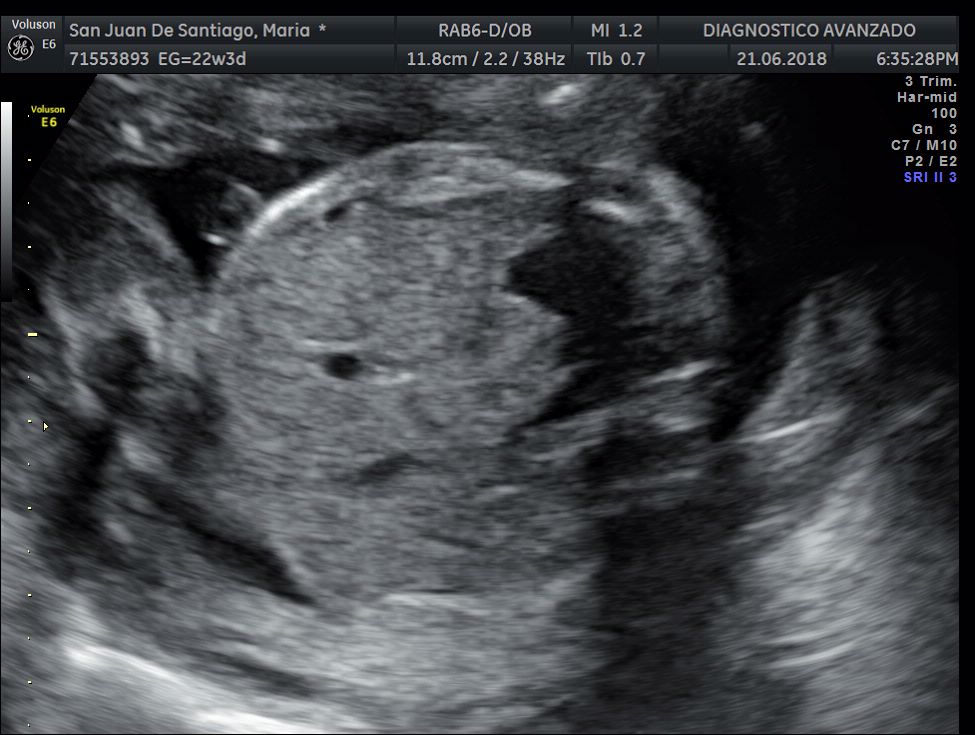

¡Hola a todos! Hoy hemos ido a hacer la tradicional ecografía 3D de la niña, os dejamos todo el material (aunque es un poco demasiado).